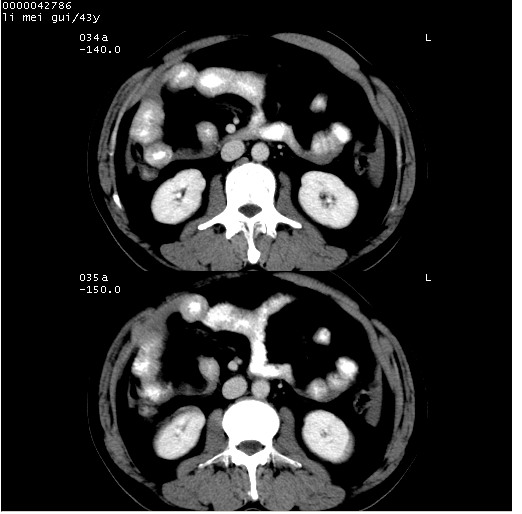

| 患者,男,43岁。突发腹痛2小时,面色苍白,难以平卧。自述近期无明确外伤史,为摩托车驾驶员。 腹部b超检查:脾脏中上极回声异常,肿瘤待排。 临床诊断:腹痛原因待查。 上中腹部ct轴位平扫+增强扫描(层厚10mm,螺距1.0,重建间隔10mm),图像如下: ![]() ![]() ![]() ![]() ![]() ![]() ![]() ![]() ![]() ![]() ![]() ![]() ![]() ![]() ![]() ![]() ![]() ![]() ![]() ![]() ![]() ![]() ![]() ![]() ![]() ![]() ![]() ![]() ![]() ![]() ![]() ![]() ![]() ![]() ![]() zrs发言:支持脾破裂 wwp发言:支持脾破裂并腹水。 xulianj发言:脾脏肿瘤破裂可能性大 zsl6918发言:不像肿瘤出血,考虑还是与外伤后引起的慢性出血有关 zzyy发言:平扫见肝周及脾周积液,脾内密度不均。脾内肿瘤较少见。还是外伤性脾破裂。 沈丘东方医院发言:脾门区一个不均匀强化病灶与其周液体相连多考虑脾占位破裂出血 yixianman001011发言:脾破裂并腹水是可以肯定的,具体原因多以肿瘤性破裂出血,脾脏淋巴瘤可能性大. 结果: 术后,经详细询问患者,其仔细回忆:一月前骑摩托时左侧腰部与别人有“轻微”触碰,因责任在自已,当时又无明显不适,未引起注意。 临床术后诊断:脾破裂并失血性休克(1.外伤性迟发性脾破裂。2.脾脏肿瘤破裂?) 术后标本病检:脾破裂并出血,未见明显肿瘤成份。 原贴地址:http://www.radinet.com.cn/forum_view.asp?forum_id=4&view_id=34070 |